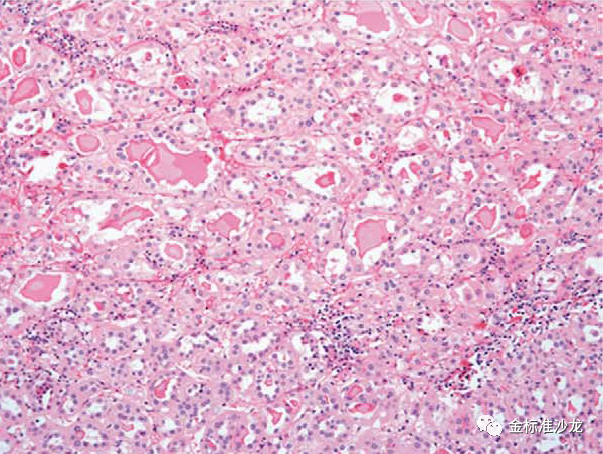

认识到pRCC在形态学存在着异质性,Delahunt和Eble首先尝试将它们分为两种类型,包括WHO2016分类仍然使用该系统且许多分子研究支持这一系统。1型pRCC通常与7号染色体(编码MET基因)17号染色体获得以及MET的体细胞激活突变相关,而2 pRCC更为异质性,且与12、16和20染色体的获得有关。1型pRCC由细乳头组成,被覆单层细胞,大多数细胞胞浆淡染,核仁不明显(图1),而2型pRCC特征包括较宽的乳头,核假复层,嗜酸性细胞质及突出核仁。然而,实际上,将pRCC一分为二可能很有挑战性,因为许多充分取材的肿瘤常常混合了类型1和类型2区域。目前的研究发现表明2pRCC可能代表几个异质性肿瘤实体,而1型pRCC基因更同质。2型pRCC核特征使这些肿瘤具有相对高ISUP的分级,可以认为不是真正代表两种独立的癌症类型,而可能代表任何pRCC从低级别到高级别的进展。重要的是, 当调整分期及其他预后因素后,1型及2pRCC并不影响患者的预后。

图1 经典的1型pRCC由纤细的乳头或管状乳头状结构组成,细胞具有淡染至嗜酸的胞浆